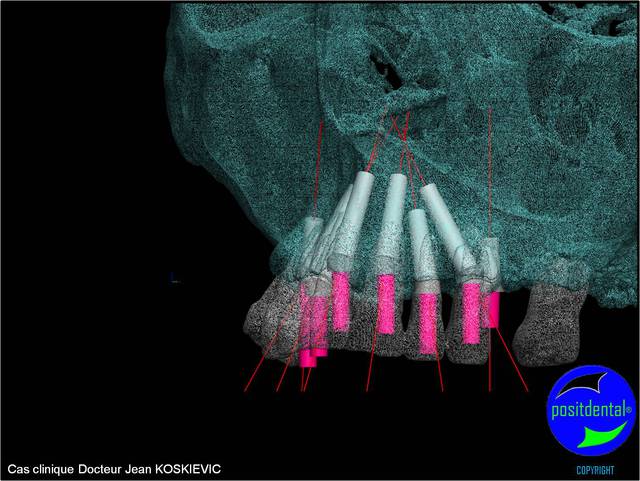

3D maxillaire inférieur et photo

Mci - Eugenol